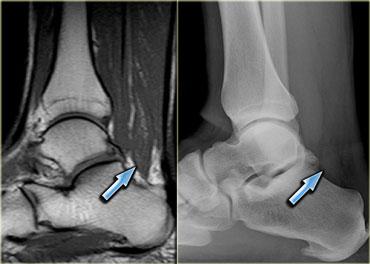

Cơ khuỷu trên ròng rọc phụ (mũi tên đỏ) – Thần kinh trụ tăng tín hiệu gợi ý viêm thần kinh trụ (mũi tên xanh)

Hình bên trái là hình ảnh khớp khuỷu, mặt trong nằm ở bên trái.

Lưu ý có một cơ nằm ngay phía sau thần kinh trụ, trong điều kiện bình thường cơ này không hiện diện tại vị trí này.

Đây là cơ khuỷu trên ròng rọc phụ (accessory anconeus epitrochlearis), gặp ở khoảng 10% dân số.

Đây là nguyên nhân thường gặp gây viêm thần kinh trụ do chèn ép, biểu hiện bằng đau và tê bì mặt trụ của bàn tay, đôi khi kèm teo cơ mô út và mô cái.

Cần quan sát kỹ thần kinh trụ khi phát hiện cơ phụ này.